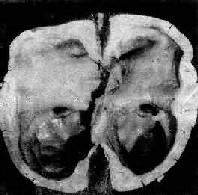

脑脊液量增多伴脑室扩张称为脑积水(hydrocephalus)。脑积水发生的主要原因是脑脊液循环的通路被阻断。引起脑脊液循环受阻的原因很多,诸如先天畸形、炎症、外伤、肿、蛛网膜下腔出血等。脑室内通路阻塞引起的脑积水称阻塞性或非交通性脑积水;如脑室内通畅而因蛛网膜颗粒或绒毛吸收脑脊液障碍所致的脑积水称交通性脑积水。此外脉络丛乳头状分泌过多脑脊液也可导致脑积水。

轻度脑积水时,脑室轻度扩张,脑组织呈轻度萎缩。严重脑积水时,脑室高度扩张,脑组织受压萎缩、变薄,脑实质甚至可菲薄如纸,神经组织大部分萎缩而消失(图16-9)。

脑积水

图16-9 脑积水

侧脑室高度扩张,脑组织受压萎缩变薄